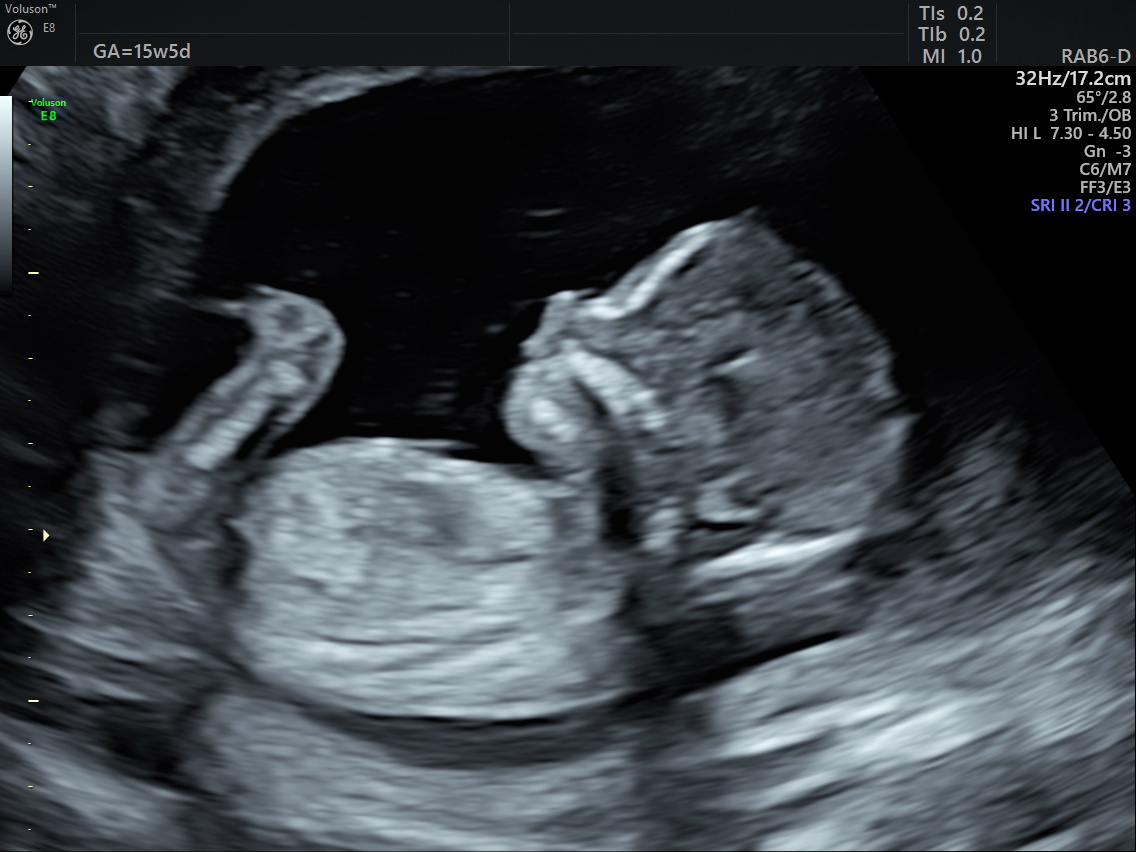

Gender scan 15 weeks onwards £85